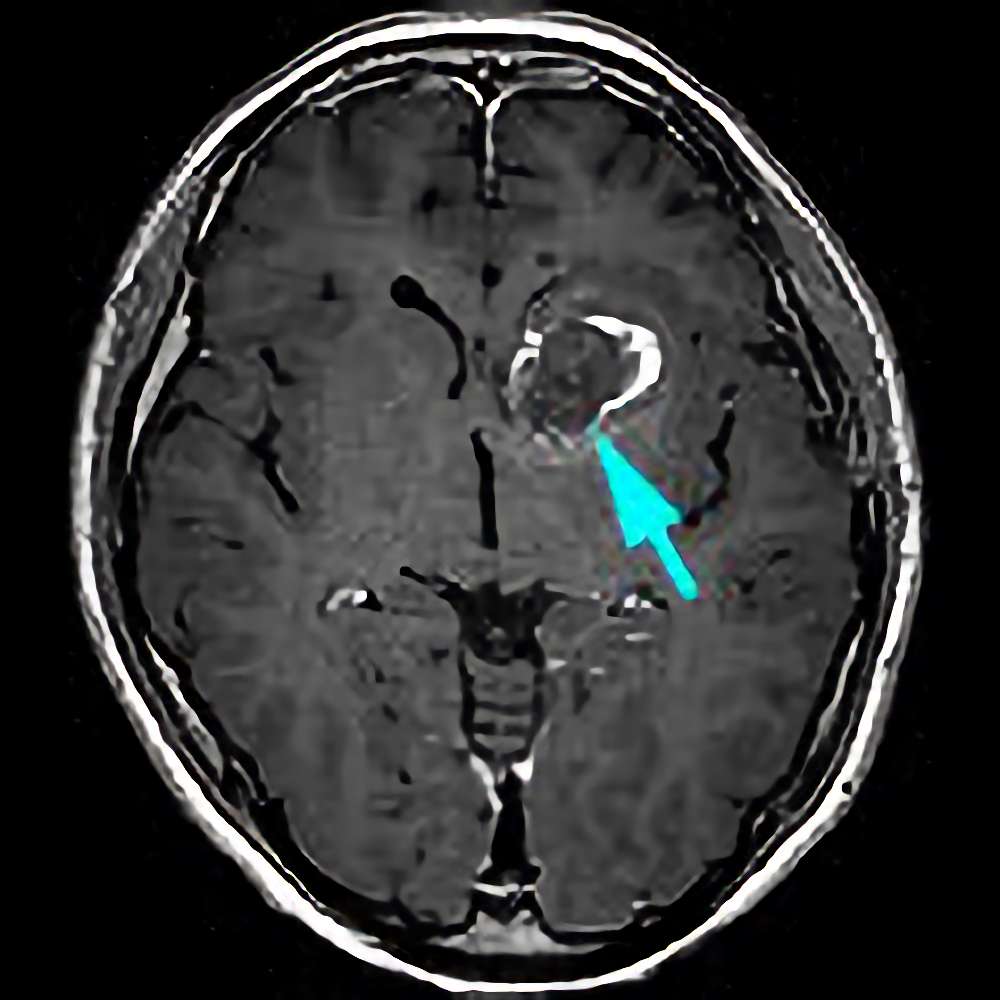

'19年11月

40代

富永

南田

基底核

海綿状血管腫

出血性

兵庫県の病院

より紹介

No.No.32 手術後1

No.No.32 手術後2

CT/MRにより完全に摘出されたことが確認された